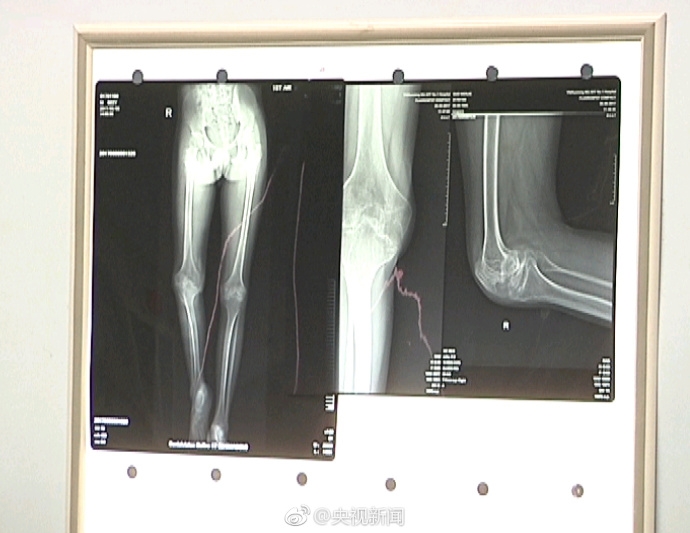

云南昆明22岁血友病患者小江,10岁时膝关节严重畸形,无法行走。但因传统关节置换手术需切开有大量血液的骨髓腔,严重危及患者生命。

十多年来,他一直没做手术。15日,小江通过3D打印技术,成功换上打印的新膝关节。康复训练3个月后基本恢复正常。祝福!(央视记者陈坚)

云南昆明22岁血友病患者小江,10岁时膝关节严重畸形,无法行走。但因传统关节置换手术需切开有大量血液的骨髓腔,严重危及患者生命。十多年来,他一直没做手术。15日,小江通过3D打印技术,成功换上打印的新膝关节。康复训练3个月后基本恢复正常。祝福!(央视记者陈坚)